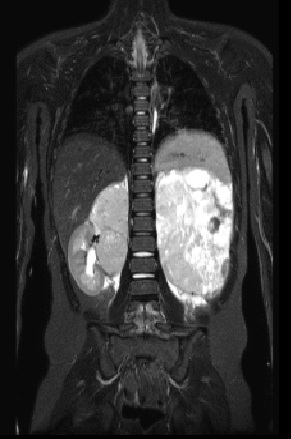

5. RMN Abdomen con contraste:

RMN: Masa retroperitoneal hipointensa en T1, realce heterogéneo con el contraste.

Hiperintensa en T2. Restringe en su mayor proporción y áreas que no restringen en relación

con áreas de necrosis.

Los estudios por imágenes identificaron una neoplasia de origen renal, una lesión tiroidea y un quiste pulmonar incidental en la TC de tórax. La anatomía patológica confirmó un nefroblastoma bilateral y un carcinoma folicular de tiroides, hallazgos que motivaron el estudio molecular confirmatorio para Síndrome de DICER1. El presente caso destaca el rol crucial del radiólogo en el reconocimiento de patrones imagenológicos sincrónicos en pediatría, fundamentales para la sospecha clínica temprana de este síndrome.